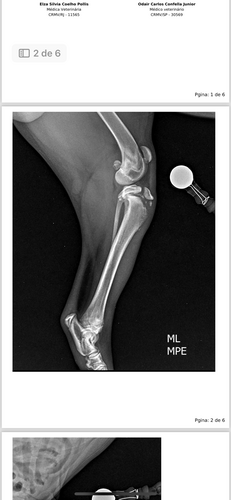

Olá me chamo Bruno tenho um filhote de Pit monster no dia 16/01/24 teve um temporal na minha região e meu Dog chamado Grego sempre fica na garagem e a noite fechamos a garagem e tem acesso uma porta da garagem para dentro de casa então ele se agitou de mais se assustou ele começou a dar pulos para tentar abrir a porta como eu trabalho de noite ele tava sozinho na garagem eu cheguei de manhã do trabalho ele estava mancando dei um anti-flamatorio para ele mas não resolveu levei no veterinário fez raio e veio a notícia que eu não queria escutar fratura na Tíbia: deslocamento proximal do centro de ossificação da crista da tíbia esquerda; ele vai precisar de cirurgia para implante, anestesia, exame de sangue raio x trans operatório eu não sei o que fazer e não tenho esse valor venho aqui pedir uma ajuda ele um bebê de 7 meses